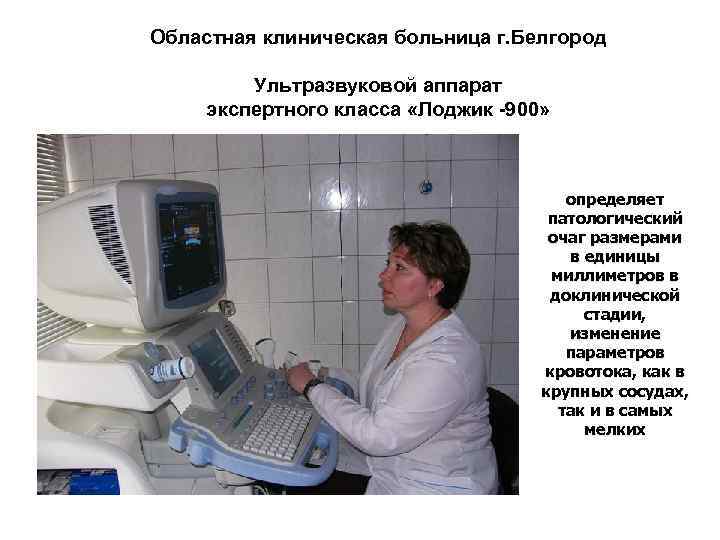

Областная клиническая больница г. Белгород Ультразвуковой аппарат экспертного класса «Лоджик -900» определяет патологический очаг размерами в единицы миллиметров в доклинической стадии, изменение параметров кровотока, как в крупных сосудах, так и в самых мелких

Областная клиническая больница г. Белгород Ультразвуковой аппарат экспертного класса «Лоджик -900» определяет патологический очаг размерами в единицы миллиметров в доклинической стадии, изменение параметров кровотока, как в крупных сосудах, так и в самых мелких